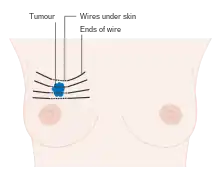

Surgery

Surgery involves the physical removal of the tumour, typically along with some of the surrounding tissue. One or more lymph nodes may be biopsied during the surgery; increasingly the lymph node sampling is performed by a sentinel lymph node biopsy.